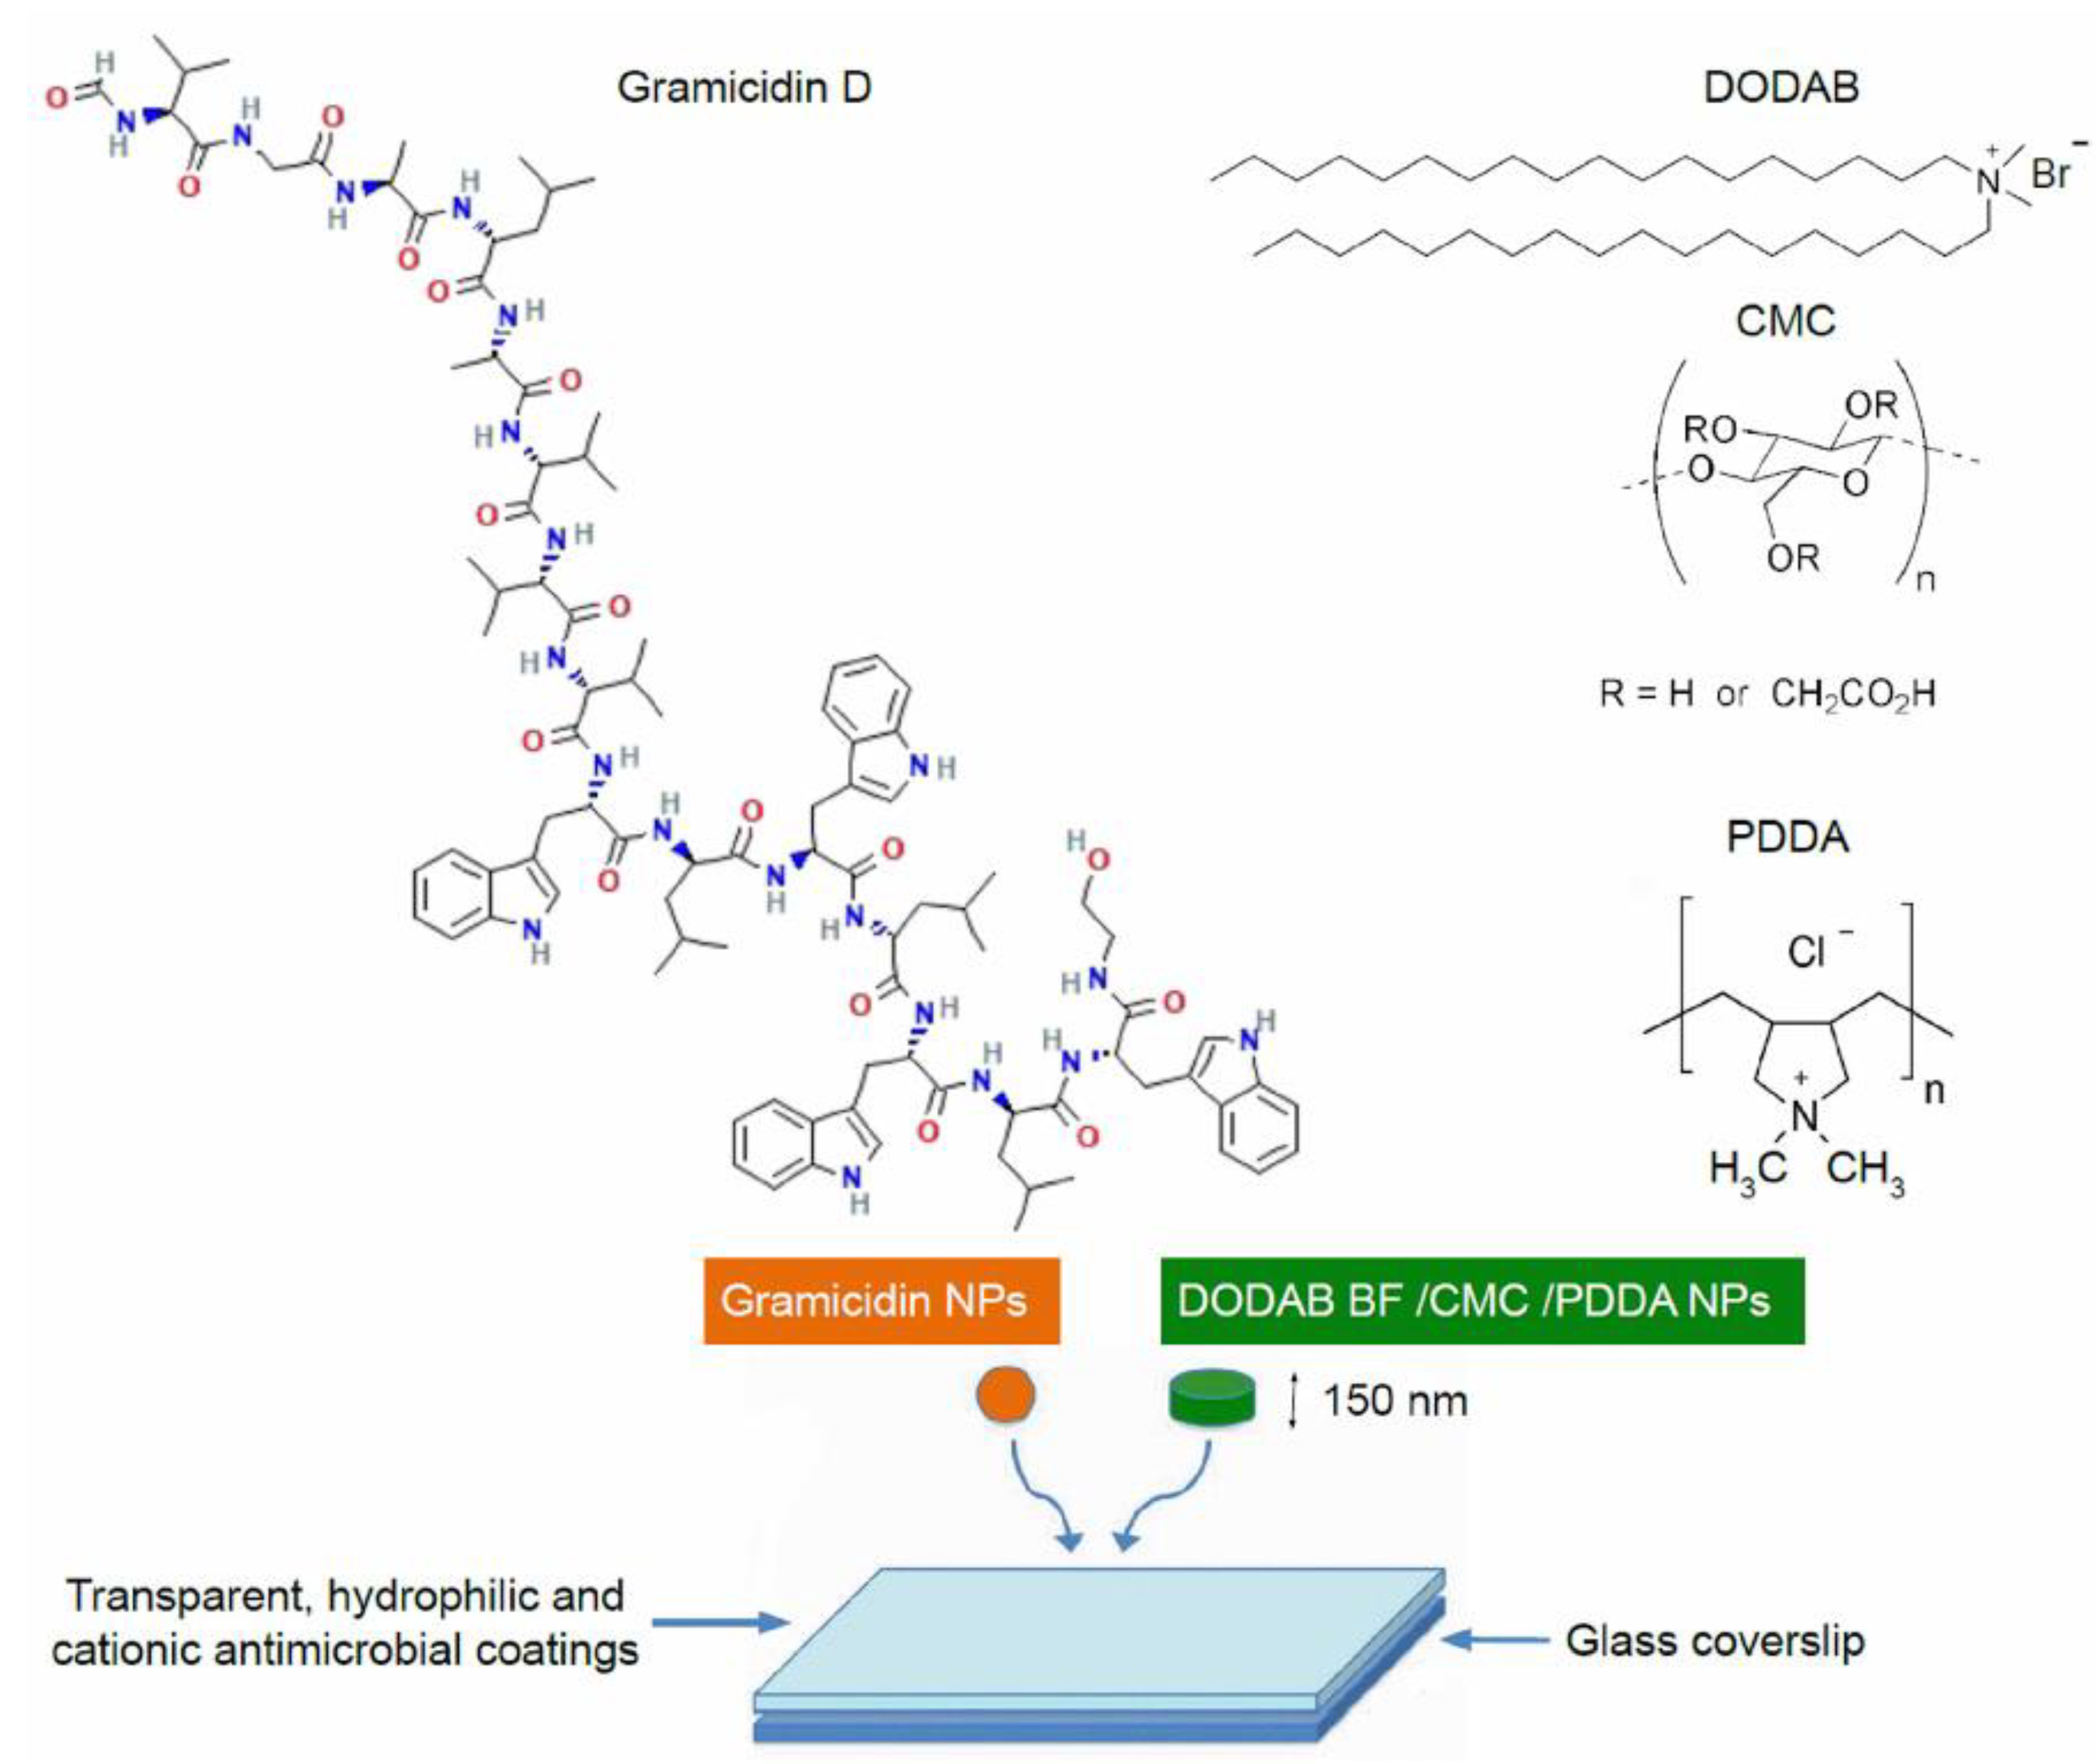

3. Gramicidin D and Its Assemblies

4. Recent Formulations for Antimicrobial Peptides